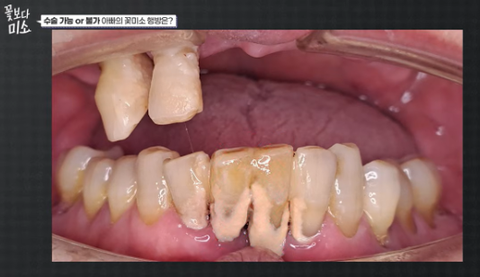

이랬던 분이

이렇게 되심 ㄷㄷ

이 상태 였는데 위쪽 임플란트 4~6개로 바뀐거

이 분이 좀 심했던거겠지..?